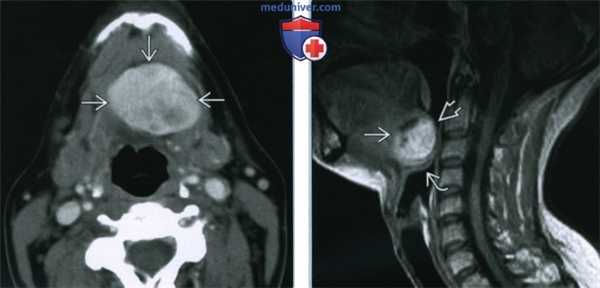

(Слева) КТ с КУ, сагиттальная проекция. Девушка с образованием в области корня языка. Срединное плотное образование, расположенное в области корня языка, вероятнее всею является эктопированной щитовидной железой. Дополнительная эктопированная ткань лежит кпереди от подъязычной кости.

(Справа) КТ с КУ у пациента с язычной щитовидной железой, аксиальная проекция. На уровне щитовидною хряща железа не определяется.

(Справа) На аксиальной КТ с КУ в основании языка по средней линии определяется округлое контрастирующееся образование с четкими контурами, с минимальной деформацией подбородочно-язычных мышц. Плотность язычной щитовидной железы намного выше по сравнению с минимально контрастирующейся язычной миндалиной. (Слева) На аксиальной КТ с КУ в области дна по средней линии определяется объемное образование с четкими контурами, представленное эктопической тканью щитовидной железы неоднородной плотности (может быть сопоставимо с ранними изменениями при зобе).

(Справа) На сагиттальной MPT (STIR, срединный срез) в основании языка визуализируется объемное образование с неоднородным гиперинтенсивным сигналом, заполняющее валлекулу. В этом случае язычная щитовидная железа обусловливает значительное сужение просвета ротоглотки, смещая надгортанник кзади и книзу.